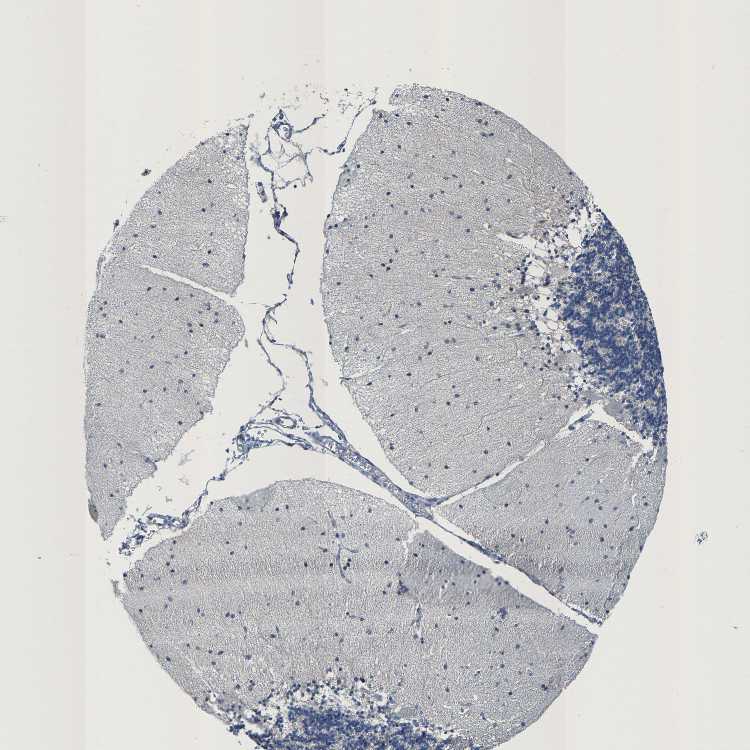

CEREBELLUM - Antibody stainingi

Antibody staining in the annotated cell types in the current human tissue is reported as not detected, low, medium, or high, based on conventional immunohistochemistry profiling in selected tissues. This score is based on the combination of the staining intensity and fraction of stained cells.

Each image is clickable and will lead to virtual microscopy that enables deeper exploration of all samples and also displays staining intensity scores, fraction scores and subcellular localization as well as patient and tissue information for each sample.

Antibody HPA021196

Purkinje cells Not detected

Cells in granular layer Not detected

Cells in molecular layer Not detected